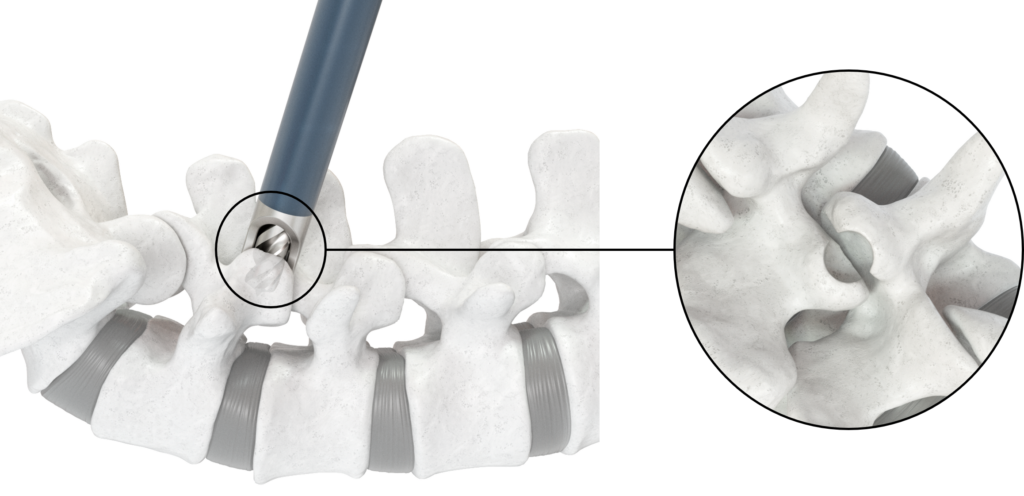

FLASH™ Facet Fusion is a navigation-compatible system that accesses the facet joints and acts as a working channel for the entire facet fusion procedure. FLASH Facet Fusion Instruments and FLASH Facet Pellets offer surgeons a technique to reproducibly locate, decorticate, and fuse in minimally invasive lumbar procedures.

Locate

Seamless integration with 7D FLASH Navigation

Real-time tool projection provides a geometric representation of the Lumbar Inserter to help target the facet joints

The navigated Lumbar Inserter guides the Facet Drill during decortication

- Inserter forks center cannula on the joint line

- Enables equal decortication of superior and inferior facets

- Drill creates a contained defect within the inserter forks

- Inserter designed to control drill depth